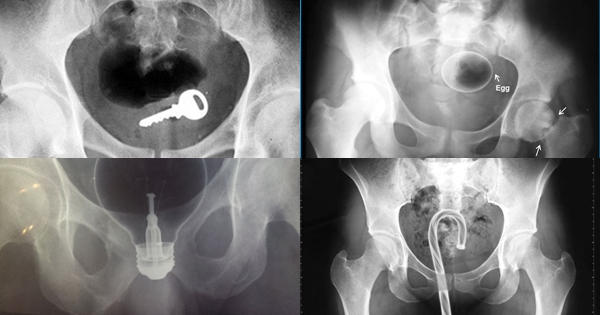

มาดูภาพเอกซเรย์ สารพัดสิ่งของที่เคยหลุดเข้าทวารหนัก

เผยภาพเอกซเรย์สุดอึ้ง สารพัดสิ่งที่เคยหลุดเข้าไปภายในทวารหนักผู้ป่วยทั่วโลก แปลกพิสดารกันจริง ๆ

การยัดสิ่งของต่าง ๆ เข้าไปในทวารหนักนั้น ไม่ว่าจะด้วยเหตุผลเพื่อหลบซ่อนการตรวจของเจ้าหน้าที่ทางการ หรือเป็นความผิดพลาดจากการแก้ขัดเมื่อเกิดอารมณ์ทางเพศก็ตาม สิ่งของที่หลุดเข้าไปนั้นล้วนแล้วแต่สร้างอันตรายให้กับอวัยวะภายในของผู้ป่วยได้หมด แต่ถึงจะเป็นอย่างนั้น เคสทางการแพทย์ว่าด้วยเรื่องของสิ่งแปลกปลอมที่หลุดเข้าไปในทวารหนักก็ยังมีให้เห็นอยู่เรื่อย ๆ ถมเถ แต่ละอย่างทำเอาอึ้ง ทึ่ง แบบไม่คิดว่ามันจะหลุดเข้าไปในทวารหนักได้จริง ๆ ดังเช่นตัวอย่างเคสที่เรานำมาฝากกันในวันนี้..

กุญแจ

ไข่ไก่